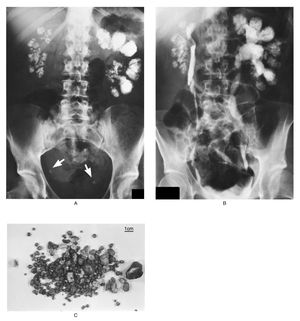

A 39-year-old woman presented with a seven-year history of renal calculi. A plain abdominal film obtained when she was 38 (Panel A) showed enlarged kidneys bilaterally with nephrocalcinosis in a papillary distribution and radiopaque calculi in both ureters (arrows). An intravenous urogram done at the same time (Panel B) showed left-sided hydronephrosis. A collection of stones passed by the patient over a two-month period is shown in Panel C. Analysis of the stones showed that the majority were composed of calcium oxalate, with some composed of magnesium ammonium phosphate. Urine cultures showed intermittent coliform infection, with no evidence of urea-splitting organisms. The patient's usual electrolyte values were as follows: serum sodium, 140 mmol per liter; potassium, 4.0 mmol per liter; chloride, 105 mmol per liter; and bicarbonate, 23 mmol per liter. Her 24-hour urinary calcium excretion (290 mg [7.2 mmol] per 24 hr) was at the upper limit of normal for our laboratory. Urinary pH was never below 6, and an ammonium chloride-loading test revealed an acidification defect consistent with the presence of type 1 renal tubular acidosis. Despite a high fluid intake (>3 liters per day) she continues to pass stones intermittently. Fortunately, her serum urea and creatinine concentrations have remained normal. Jonathan T.C. Kwan, M.D. Frank P. Marsh, M.A., F.R.C.P. Royal London Hospital, London E1 1BB, United Kingdom Source: nejm.org